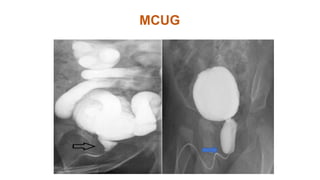

MCUG- Diagnostic • Dilatation and elongation of posterior urethra.

• Distal urethral stream is narrow

• Bladder may show irregular border.

MCUG